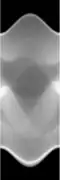

Concretely, for the two-dimensional Radon transform, the dual transform is given by: In the context of image processing, the dual transform is commonly called back-projection[4] as it takes a function defined on each line in the plane and 'smears' or projects it back over the line to produce an image.

In the two-dimensional case, the most commonly used analytical formula to recover from its Radon transform is the Filtered Back-projection Formula or Radon Inversion Formula[9]: where is such that .[9] The convolution kernel is referred to as Ramp filter in some literature.

Explicit and computationally efficient inversion formulas for the Radon transform and its dual are available. The Radon transform in dimensions can be inverted by the formula:[11] where , and the power of the Laplacian is defined as a pseudo-differential operator if necessary by the Fourier transform: For computational purposes, the power of the Laplacian is commuted with the dual transform to give:[12] where is the Hilbert transform with respect to the s variable. In two dimensions, the operator appears in image processing as a ramp filter.[13] One can prove directly from the Fourier slice theorem and change of variables for integration that for a compactly supported continuous function of two variables: Thus in an image processing context the original image can be recovered from the 'sinogram' data by applying a ramp filter (in the variable) and then back-projecting. As the filtering step can be performed efficiently (for example using digital signal processing techniques) and the back projection step is simply an accumulation of values in the pixels of the image, this results in a highly efficient, and hence widely used, algorithm.